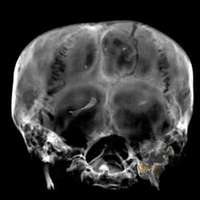

Ampliar la imagen Vista de la parte anterior del cr�o del fara�gipcio Tutankam�OTO Reuters

Investigadores de Egipto, Suiza e Italia refutan con una tomografía computarizada la teoría más aceptada hasta ahora. Hace años, unas radiografías detectaron una astilla de hueso en la parte anterior del cráneo. Los historiadores llevan años intentando descubrir la causa de la muerte del faraón.

El nuevo análisis, sin embargo, no halló ningún indicio de que el faraón falleciera como consecuencia de un golpe en la cabeza. Lo que no se descarta es que Tutankamón muriera asesinado de otra manera, quizá envenenado o estrangulado. También es posible que por causas naturales.

La cabeza algo alargada entra en el ámbito de lo normal, añade el informe de los especialistas. Y la poco habitual flexión de la columna vertebral presumiblemente se debe a la postura del cuerpo al ser embalsamado.

La tomografía computarizada aportó indicios acerca de que Tutankamón se fracturó el fémur izquierdo poco antes de morir. Pero ésa no pudo haber sido la causa de su deceso, señaló el Consejo Egipcio de Antigüedades.

A principios de enero se tomaron mil 700 imágenes del faraón con el tomógrafo. Era la primera vez que se realizaba esta prueba a la momia.